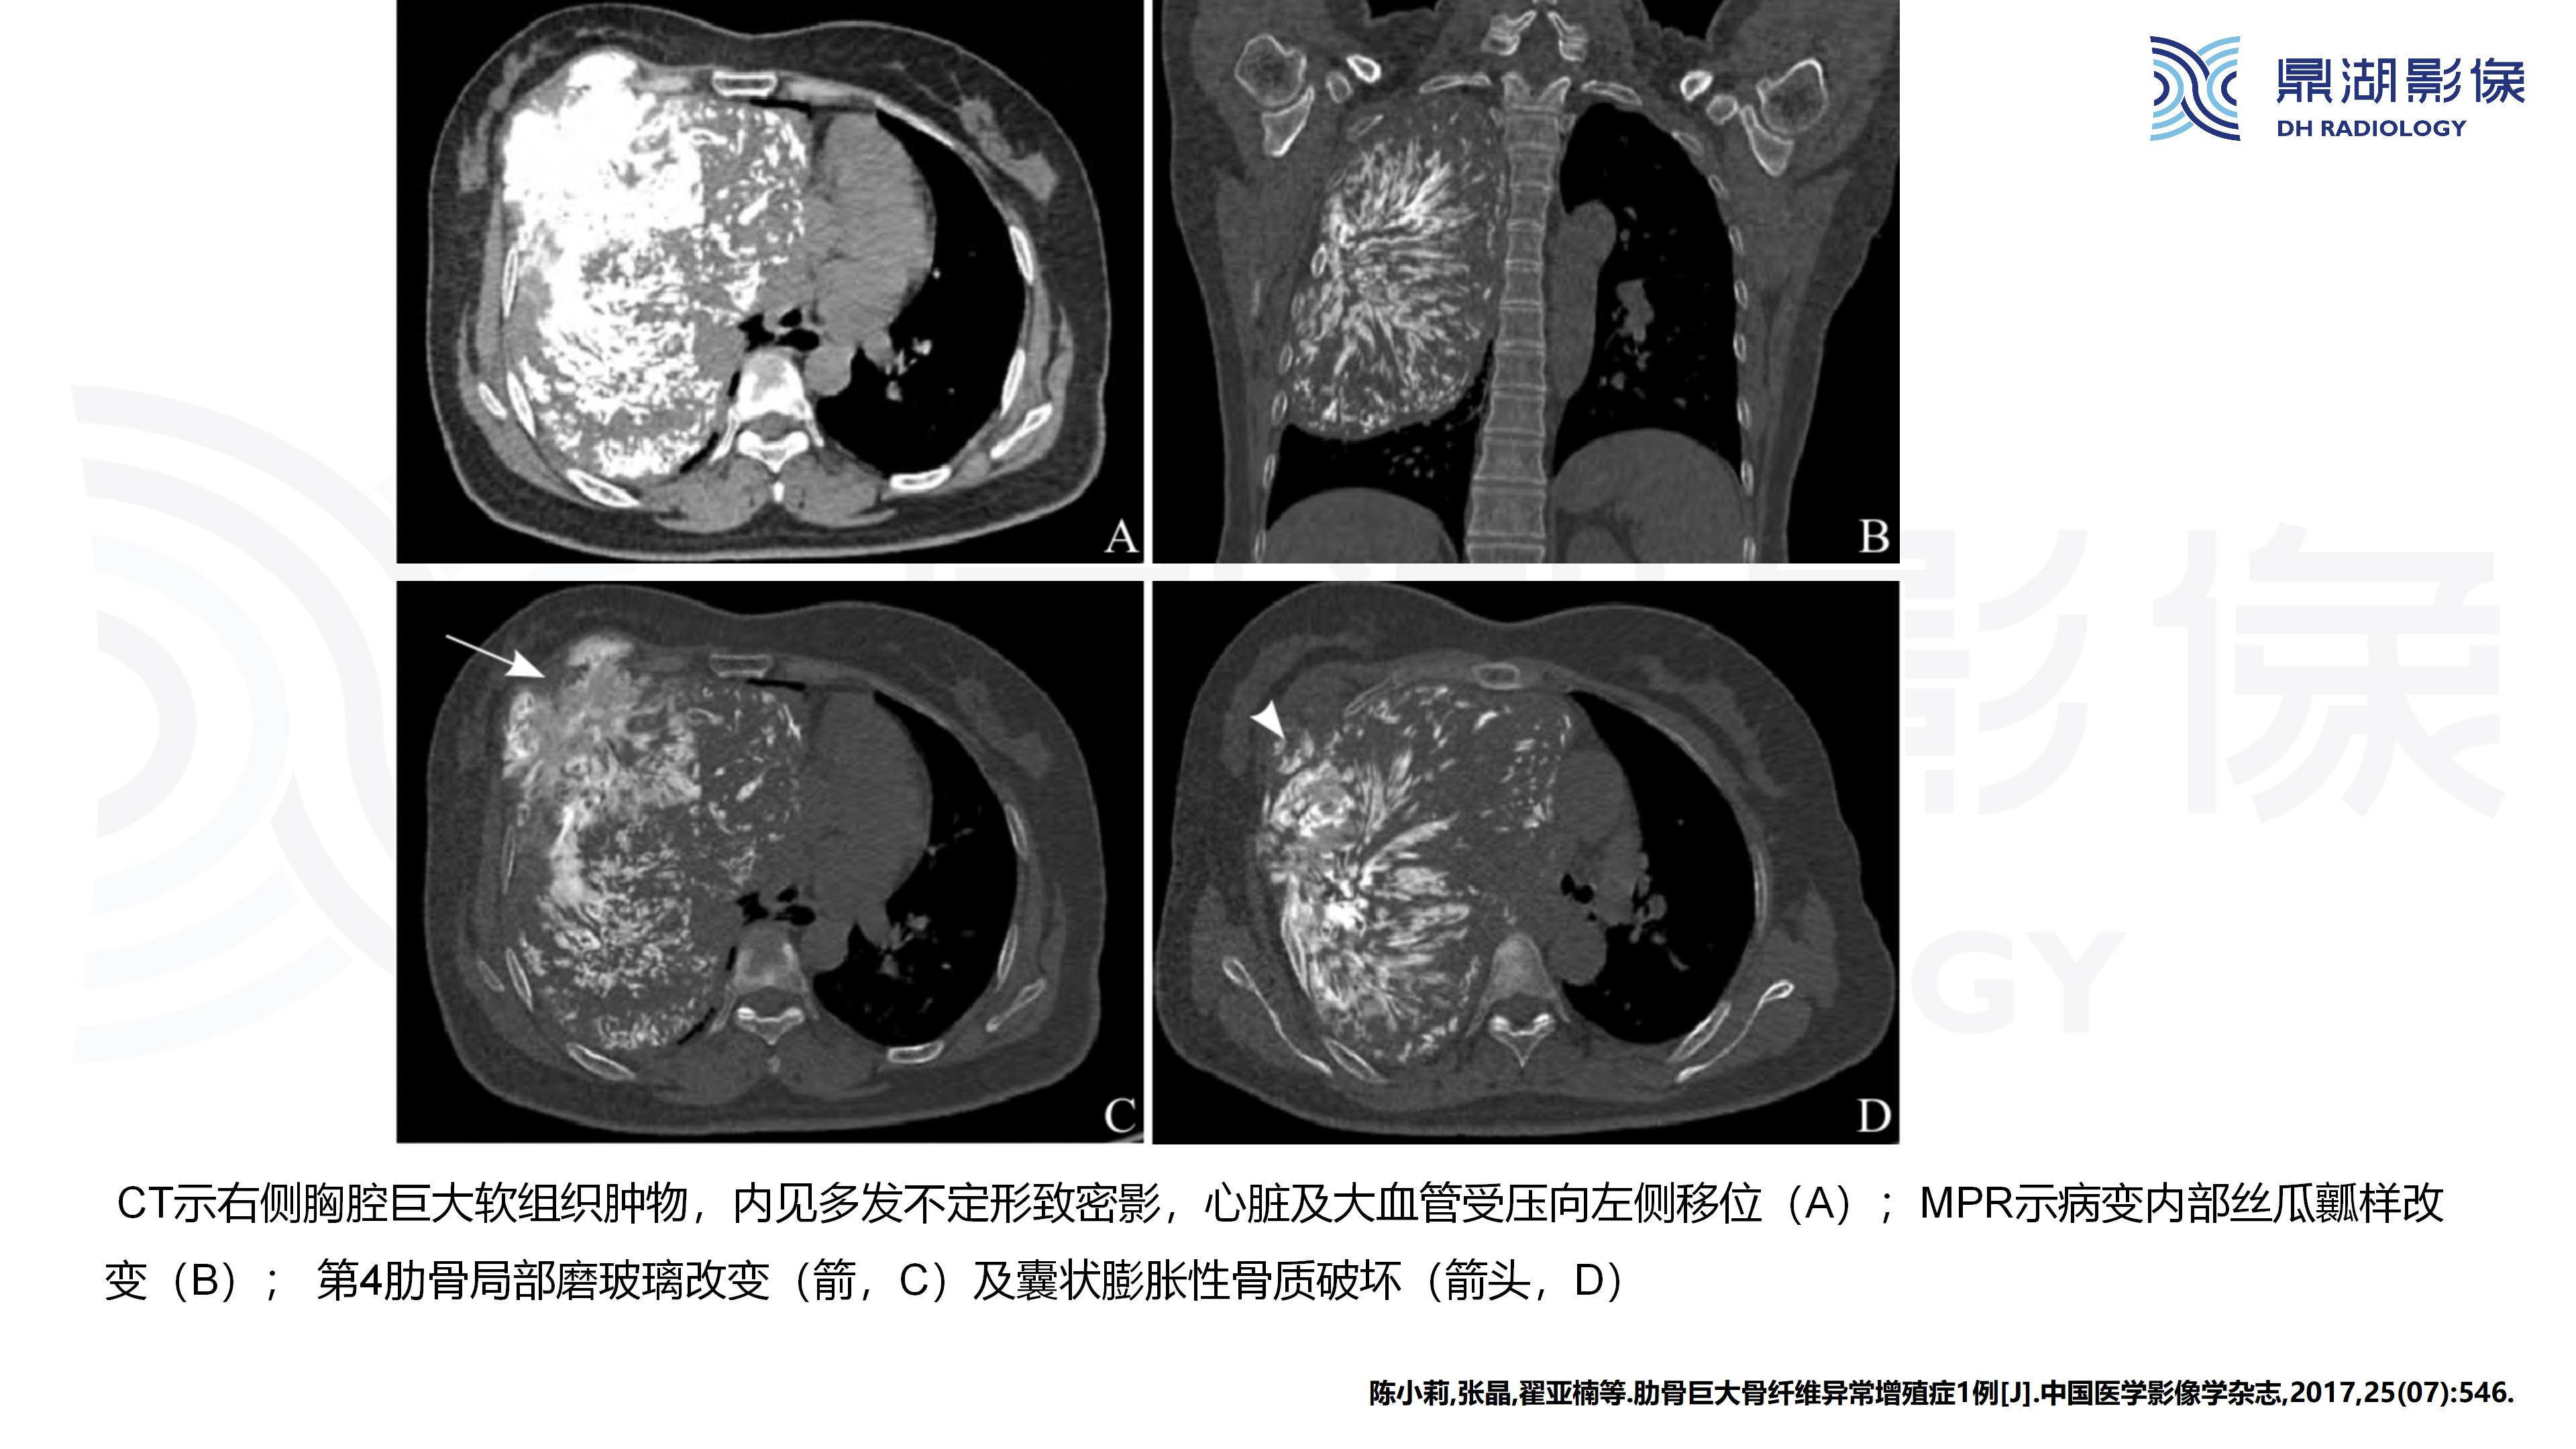

现病史:患者女,63岁,半年前活动后出现左侧胸痛,轻度胸闷,无咳嗽咳痰,无头痛头晕,无恶心呕吐,无腹痛等不适。温州大学第一附属医院就诊,未行治疗。半年来左侧胸壁隆起较前明显,活动后轻度胸痛症状,余无明显不适。